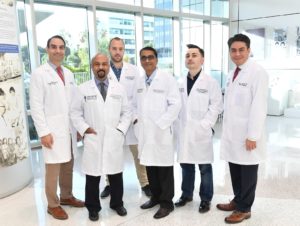

Breakthrough Therapy for Prostate Cancer

Przemyslaw W. Twardowski, M.D., medical oncologist and professor of medical oncology and urologic oncology at the Saint John’s Cancer Institute…